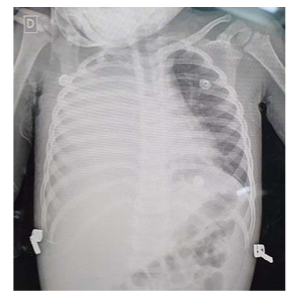

Uma menina de um ano e sete meses de idade foi levada ao pronto-socorro com queixa de dor abdominal, vômitos e febre (39 ⁰C) há dois dias. Sua mãe referia resfriado há dez dias, com piora há três dias. Exame físico: REG; descorada 2 +/4+; anictérica; acianótica; afebril; taquipneica; FR de 50 irpm; FC de 140 bpm; PA de 85 x 50 mmHg; sat. de O2 de 91% em ar ambiente; MV+, abolido em 2/3 inferiores do hemitórax direito; broncofonia diminuída em base direita; e tiragem subcostal. Exames: Hb 9.5 g/dl; Ht 27%; leucócitos 26.500, com desvio à esquerda; e PCR 25 mg/dl.

Com base nesse caso hipotético, assinale a alternativa incorreta.